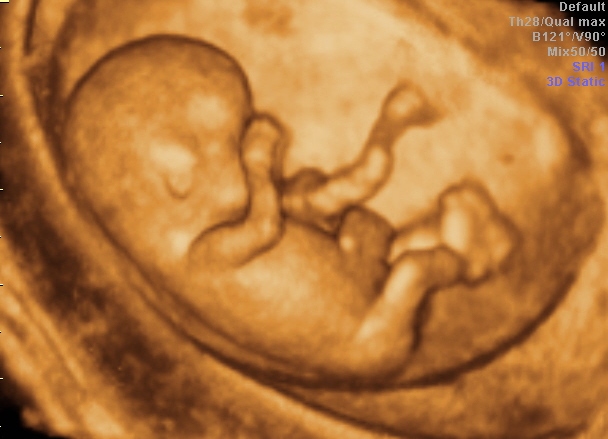

• 3D- und 4D-Sonographie

• Nackentransparenzmessung und „Firsttrimester-Screening“

• zusätzliche Schwangerschaftsultraschalluntersuchungen

• Nackentransparenzmessung in der Frühschwangerschaft zur Bestimmung des Mißbildungsriskos chromosomaler Erkrankung (zertifiziert nach Richtlinien der Fetal Medicine Foundation)